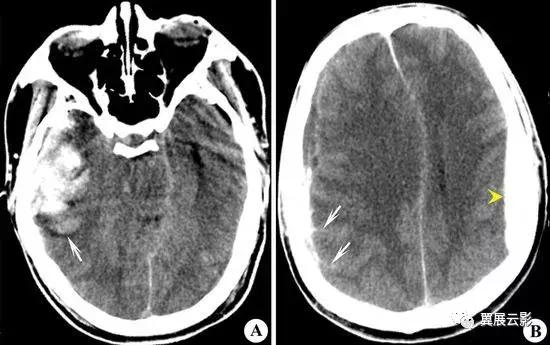

病例2:硬膜下血肿(亚急性期)

报告中重点描述硬膜下血肿的形态,信号,脑回推挤征及占位效应,诊断中应注意与硬膜外血肿相鉴别。

病例3:硬膜外血肿(超急性期)

书写报告时重点描述血肿的形态,部位,大小,信号及占位效应,鉴别诊断时重点与硬膜下血肿相鉴别。